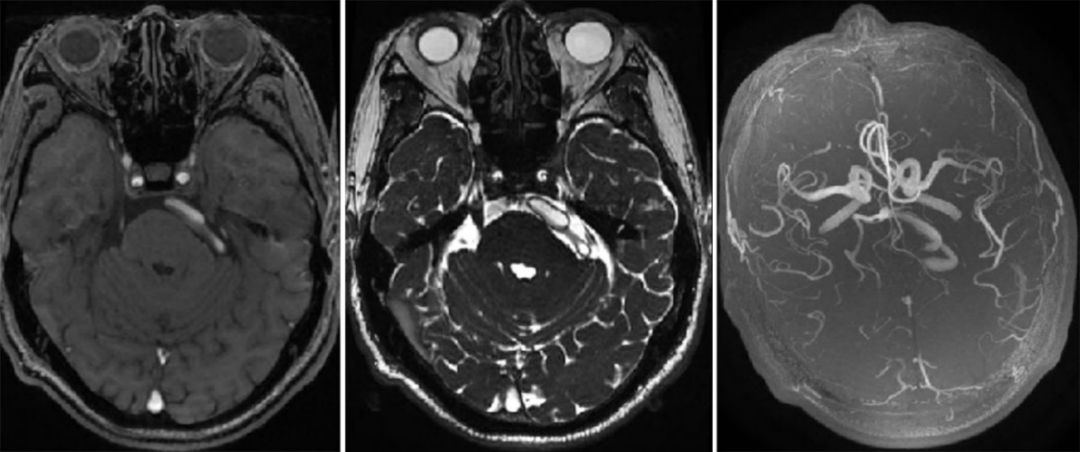

三叉神经痛的病因存在各种争论,具体机制仍有待研究。针对椎基底冗长扩张引发三叉神经痛的患者,为了最大限度地发挥治疗效果,我们通过切开小脑幕减少了对三叉神经的压迫。这种方法简单而安全,可能是治疗VBD引起的三叉神经痛的新方法,但具体疗效还需更多的病例和长期随访去证实。